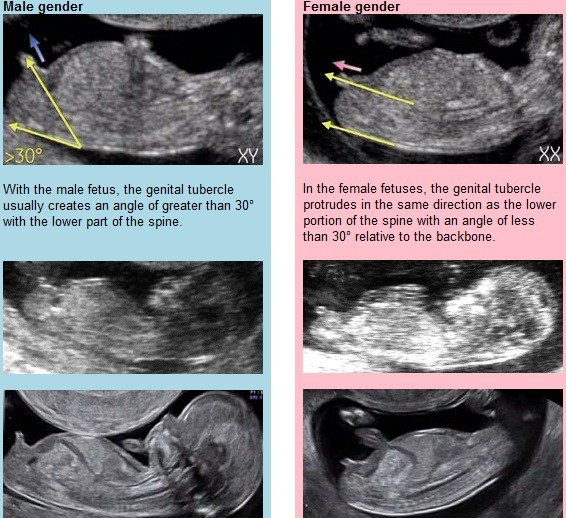

Avendo già 2 maschi il desiderio che questa volta sia una femmina è davvero tanto! E così ho letto un pò in internet e ho trovato tanti giochi (il pendolo, le lune, i capelli dei bambini già avuti, ecc… ecc…) ma nessuno con teoria scientifica! E invece una teoria scientifica esiste! Da mettere in pratica tra la 11esima e la 14esima settimana, valutando il tubercolo, la protuberanza simile a un pisellino che in questa epoca gestazione hanno sia le femmine che i maschi! Dopo tale data un ecografo esperto può distinguere un chicco di caffè (3 lineette) per individuare una femmina o un pisellino.

Ma veniamo a noi, come capire il sesso grazie alla ecografia del primo trimestre? Innanzitutto va detto che 1 su 5 è il margine di errore. Quindi questa teoria si, è su base scientifica, ma non è certezza! Quindi aspettate di comprare i primi vestitini, anche se la tentazione è davvero tanta!

Ieri ho avuto la translucenza nucale, e dopo aver stabilito che il rischio delle 3 malattie più comuni è bassissimo, ho chiesto al ginecologo, mi è capitato l’ecografo più bravo della mia zona (questa è la sua fama), se poteva darmi un idea del sesso, ha provato a fare il simpatico dicendomi la percentuale di possibilità che sia femmina…50% ma va!!! Non mi è stato molto di aiuto. Ma la mia curiosità non si è fermata! E così gli ho detto che la notte precedente ero stata sveglia fino le 2 del mattino a studiare la NUB THEORY. Cosa ne pensa lui? Pensa che è una teoria valida ma non certa (ci prende nell’80 dei casi) ma per metterla in pratica bisogna riuscire ad avere una ecografia con il bimbo perfettamente di lato, e bisogna vedere il tubercolo molto nitido!

Ho trovato una foto in Google che spiega la teoria con immagini, così da farla capire bene anche a voi: